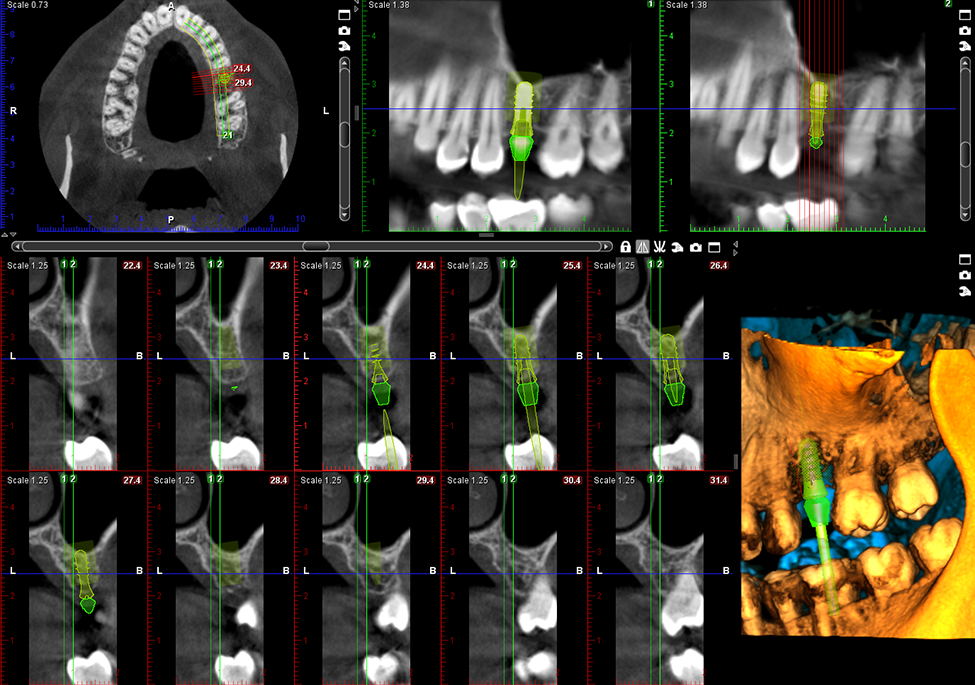

Dental Imaging

img01

Planmeca ProMax 3D

• Low-radiation 3D CBCT scans for safer, more accurate diagnosis of teeth, jaw, and sinus problems.

• Fast and comfortable imaging completed in seconds.

• 3D facial photo with zero radiation to help plan cosmetic and orthodontic treatments more precisely.

• Precise digital models for better-fitting treatments like implants, aligners, and restorations.